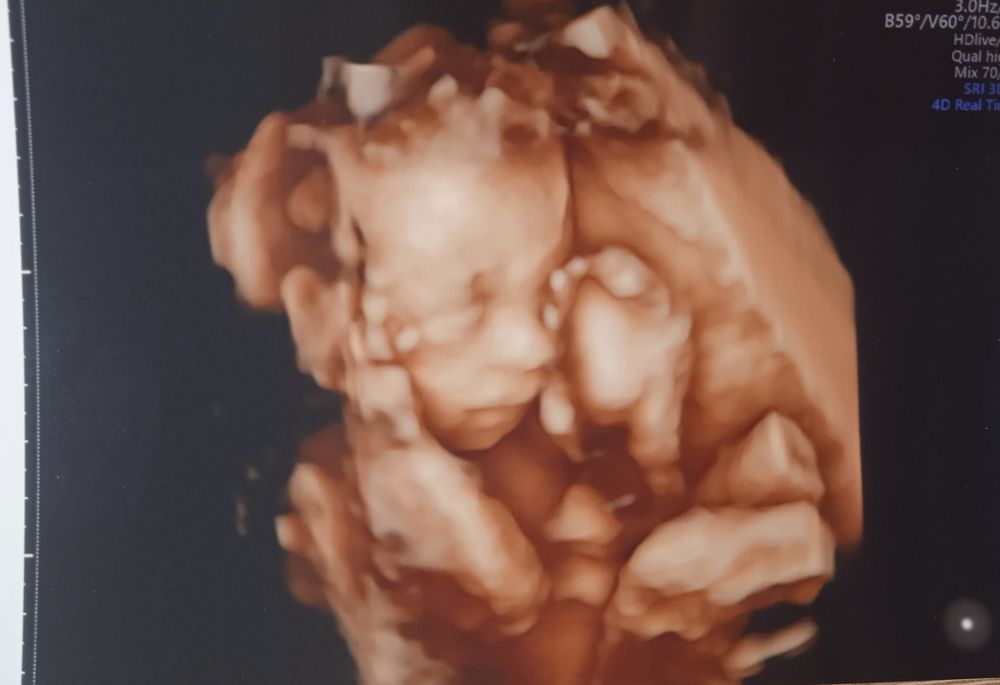

Анастасия, вот ещё 30,6 и 11,1 неделек, качество там отличное, аппарат последнего поколения